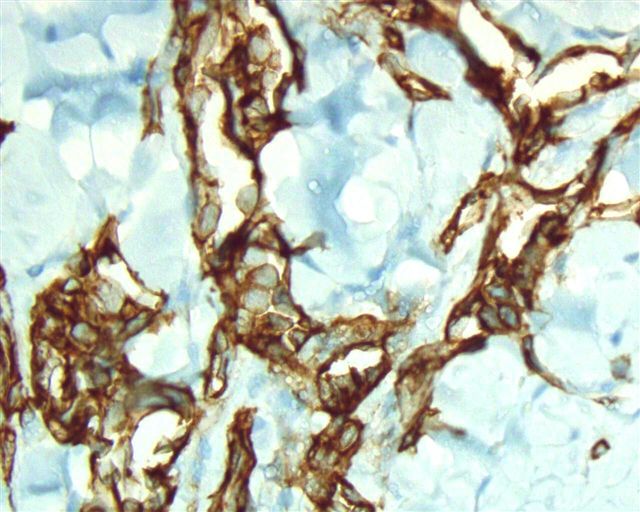

Microscopic (histologic) images

Positive stains

- CD31: membranous staining

- CD34: membranous staining

- ERG: nuclear staining

- Claudin5: cytoplasmic staining (Am J Surg Pathol 2011;35:1848)

- VEGFR2: membranous staining (Am J Surg Pathol 2012;36:629)

- PROX1: nuclear staining (Am J Surg Pathol 2012;36:351)